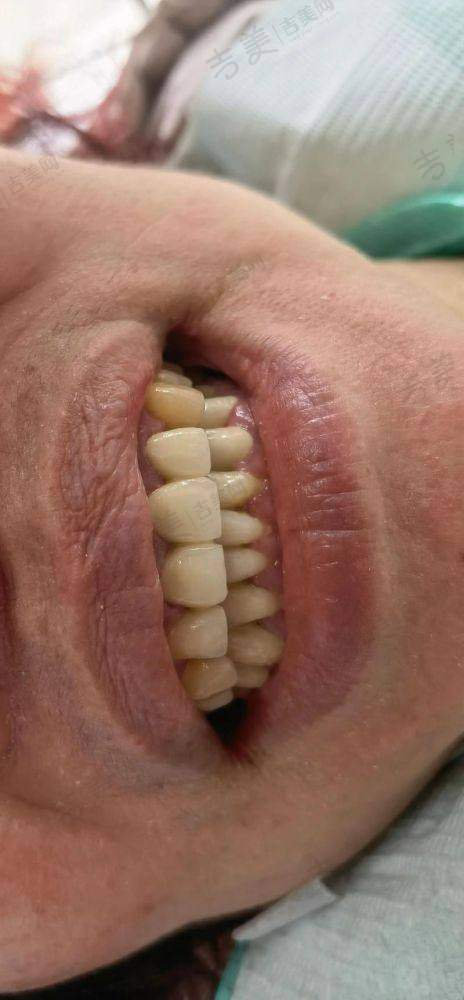

丰富手术项目:上海雅杰口腔诊所诊疗项目丰富,规模适中且科室设置较为齐全。其诊疗科目涵盖口腔科、牙体牙髓病、牙周病、口腔粘膜病、儿童口腔、口腔颌面外科、口腔修复、口腔正畸、口腔种植、预防口腔,还有医学影像科的X线诊断。在手术方面,诊所擅长种植牙手术,无论是前后牙种植,还是内/外提、各类骨增量、穿翼、半/全口即刻种植手术都能熟练开展;牙齿矫正手术也特别出色,包括成人正畸和儿童早期干预;牙齿修复手术同样是其优势,如全口活动义齿修复、美学修复等;此外,在各类阻生智齿拔除、规范化根管治疗、牙周治疗等方面也有丰富的经验和专精的技术。凭借这些优势手术项目,为不同口腔问题的患者提供了有效的治疗方案。

特色科室与项目:上海雅杰口腔诊所的科室设置和特色项目优势明显。科室方面,有口腔科、牙体牙髓病科、牙周病科等多个专精科室。特色项目包括种植牙、牙齿矫正、牙齿修复、儿童牙齿治疗等。种植牙项目采用数字化种植,拥有3D导板种植系统,可精细定位种植位置,减少创伤,修复更快。牙齿矫正中的隐形矫正使用口内扫描仪,5分钟扫描取模,不用咬恶心的石膏,还能即时出3D矫正方案。牙周治疗采用超声波洁牙机 + 激光治疗仪,洁牙更干净,激光消炎减少出血,不适感轻。儿童补牙配备疼痛较小局麻仪 + 卡通牙钻,缓慢给药减少疼痛,卡通造型缓解孩子紧张。这些特色项目凭借精良的设备和专精的技术,为患者提供了优质的口腔治疗体验。

合理亲民的价格:上海雅杰口腔诊所收费合理,价格亲民。常见项目价格如下:超声波洁牙168元起,儿童乳牙拔除29.9元起,窝沟封闭308元起,上颌正位智齿拔除780元起,冷光牙齿美白1180元起,全瓷牙冠1980元起,爱尔创全瓷牙2980元起,德国威兰德全瓷牙4980元起,瓷贴面美白2900元起,成人树脂补牙299元起,时代天使隐形矫正16800元起,国产传统金属托槽矫正8999元起,儿童早期干预矫正32000元起,瑞士士卓曼iti标准版种植牙8999元起/颗,德国贝格种植牙6999元起/颗,韩国dio种植牙2680元起/颗,美国皓圣种植牙4588元起/颗。老年人种牙价格方面,all - on - 4种植牙4593元起,种植牙纯钛桥架5463元起等。此外,该诊所在暑期还有优惠,如韩国种植体一颗特价3999元起,品牌二氧化锆全瓷牙2980元/颗起,传统金属托槽矫正特价9800元起,日式PMTC八步高端舒适洁牙980元起 。